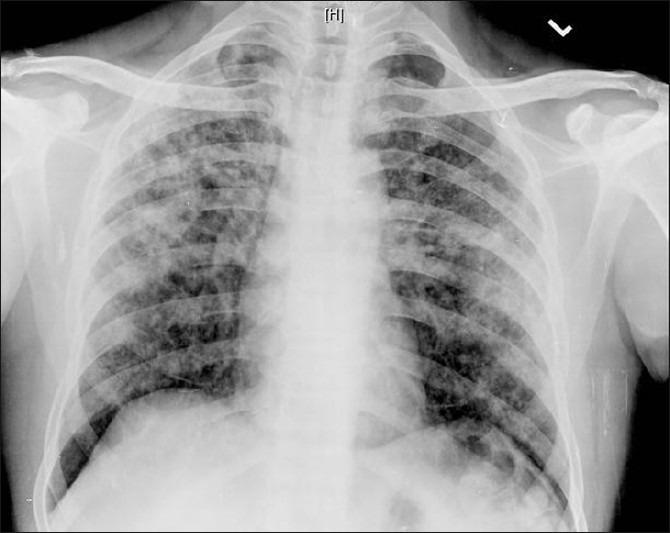

Tuberculosis of the oral cavity is a rare condition. A 55-year-old labourer was referred as a case of oral cancer for further management. The patient had no systemic symptoms. Biopsy of the lesion revealed caseating granulomatous inflammation. Chest X-ray and sputum revealed evidence of asymptomatic pulmonary tuberculosis. The purpose of this paper is to sensitize clinicians to consider oral tuberculosis as a differential diagnosis in patients with an Non-healing oral cavity ulcer.

口腔结核是一种罕见病症。一名55岁的劳工被转诊为口腔癌病例以进行进一步治疗。该患者无全身症状。病变组织活检显示干酪样肉芽肿性炎症。胸部X光检查和痰液检查发现无症状性肺结核的证据。本文旨在提高临床医生对口腔结核的认识,使其在患有不愈合口腔溃疡的患者中将其作为鉴别诊断考虑。